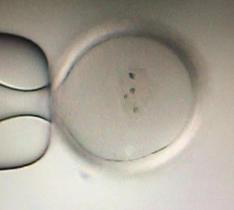

普通倒置镜下ICSI

纺锤体观察下ICSI

经过IVM培养后,即便是MI的卵母细胞,只要看到纺锤体就行ICSI,术后行卵子激活技术(AOA)。这样大多数卵子能正常受精和继续发育,达到第三天胚胎冷冻标准或进行囊胚培养,形成可冷冻的囊胚。有几位幸友在移植后成功受孕并最终take baby home。